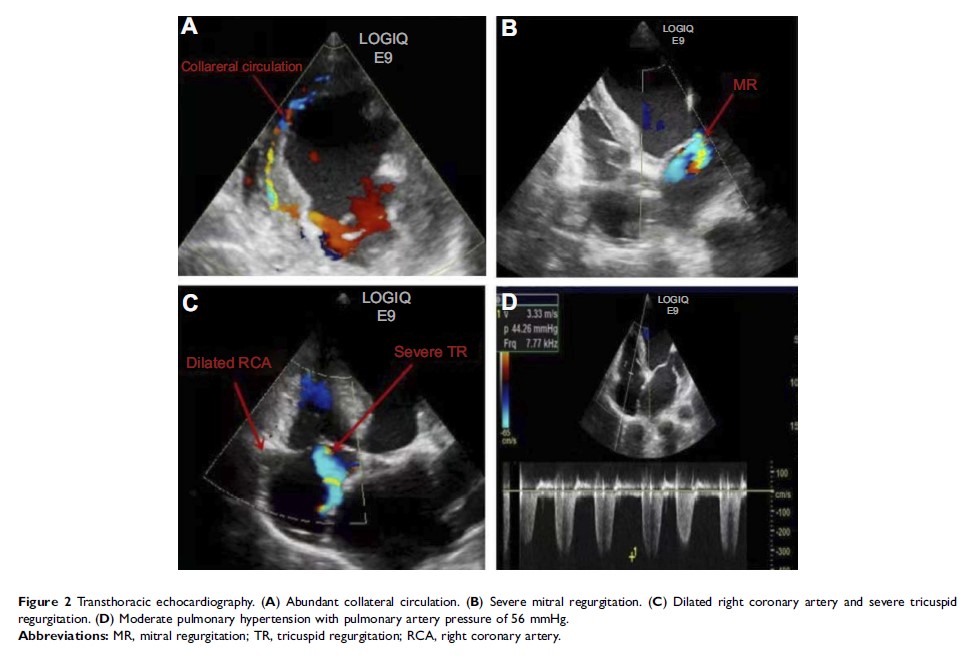

未经手术修复的 Bland-White-Garland 综合征麻醉管理1例并文献回顾